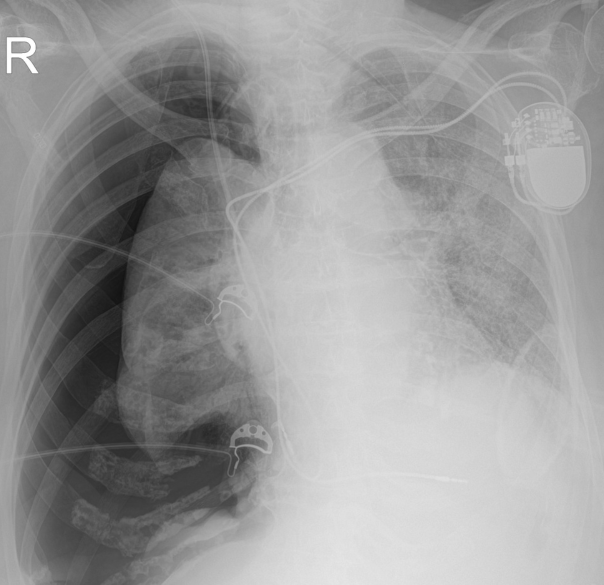

penumothorax

Signes Surajoutés

- Déviation du médiastin

- Abaissement de la coupole diaphragmatique

- Ecartement des cotes